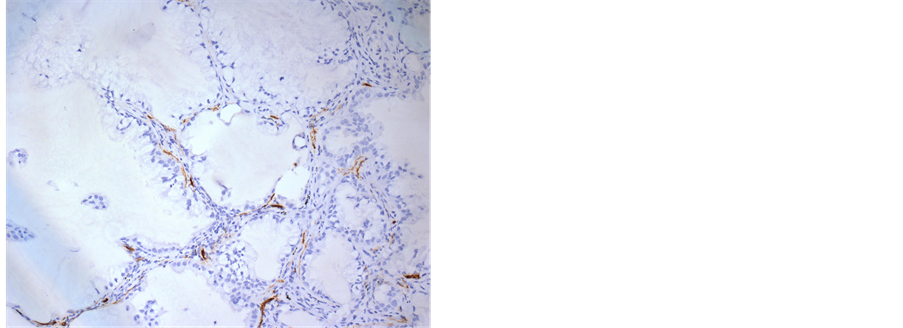

To measure the expression of CD34 and F8, immunohistochemistry was performed. Strong positive expression of CD34 was observed in the basement membrane of AIS, while moderate positive expression of CD34 was observed in interstitial cells of AIS (Figure 1(a)). In addition, strong positive expression of CD34 was observed in the basement membrane and interstitial cells of adherent adenocarcinoma of MIA and IA (Figure 1(b)). All interstitial cells of acinar adenocarcinoma in MIA and IA showed negative expression of CD34, but acinar adenocarcinoma with non-invasive growth was surrounded by basement membranes with positive expression of CD34 (Figure 1(c)), and acinar adenocarcinoma with invasive growth was not surrounded by CD34-positive basement membranes (Figure 1(d)). In CD34 staining images, it is difficult to discriminate tumor interstitial cells with positive expression of CD34 from vascular endothelia. And the vascular endothelial cells showed positive expression of CD31 and F8. By comparing CD31 and F8 staining images, basement membranes with positive expression of CD34 were differentiated from interstitial cells (Figure 1(b) and Figure 2(a), Figure 2(b)). The basement membranes and interstitial cells of AAH had negative or weak positive expression of CD34 (Figure 1(e)). Other invasive cancers such as papillary adenocarcinoma, micropapillary adenocarcinoma and solid adenocarcinoma were not surrounded by basement membranes, but their interstitial cells had negative CD34 expression. In addition, the basement membranes and interstitial cells of noncancerous alveolar tissues and mucinous adenocarcinoma had no CD34 expression (Figure 1(f)). The vascular endothelial cells in all groups showed positive expression of CD34. Statistical analysis showed that the average CD34-positive expression score of IA patients was significantly lower than those of AAH, AIS and MIA patients (P < 0.05) (Table 2). These results suggest that the basement membranes and interstitial cells of AAH, AIS and the AIS component of MIA have positive expression of CD34, while mucinous AIS and various invasive adenocarcinomas have no CD34-positive basement membranes or interstitial cells.

Figure 1. Immunohistochemical staining of CD34 in (a) adherent adenocarcinoma (Noguchi type A) (×200), (b) adherent adenocarcinoma (Noguchi type B) (×100), (c) alveolar adenocar-cinoma of MIA (×100), (d) adherent adenocarcinoma (upper half) and alveolar invasive adenocarcinoma (lower half) (×50), (e) AAH (×100), and (f) mucinous adenocarcinoma (×50).